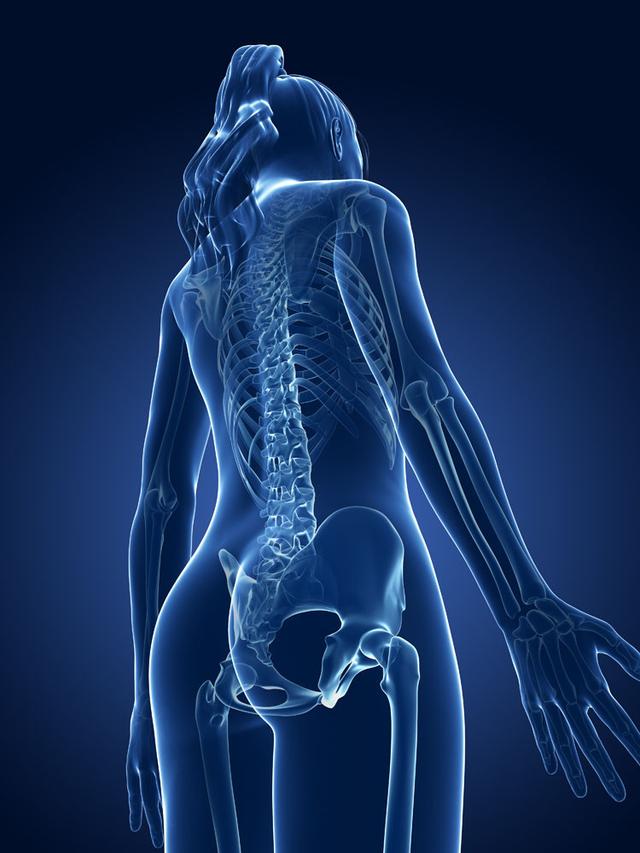

从一方面来说,人类是弱小的,容易生病,容易受伤,但从另一方面来说,人类也是强大的...